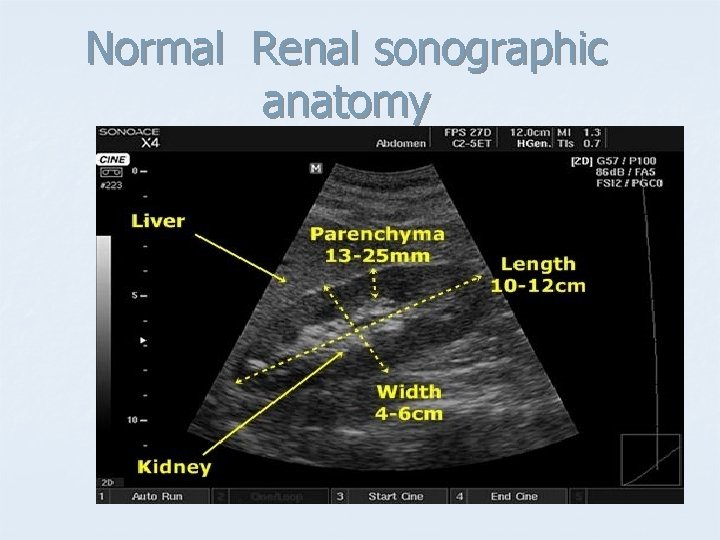

Normal Renal sonographic anatomy